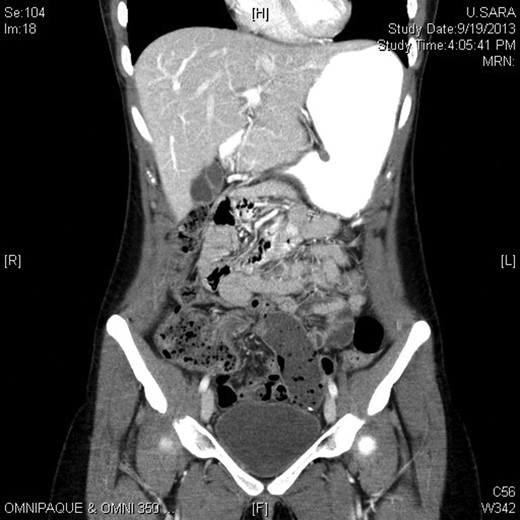

Six days later, the patient returned to the emergency room with abdominal pain for <12 h in the periumbilical region. The pain was worse than when she had appendicitis. She reported chills, nausea and vomiting. On examination, she was tender in the periumbilical region and mildly distended. She underwent CT scan, which showed a small bowel obstruction with a transition point in the right lower quadrant (Fig. 1). She was taken to the operating room for an exploratory laparoscopy. A staple attached to the appendiceal stump on one end had snagged a loop of small bowel and small bowel mesentery with the other end (Fig. 2). It was causing an internal hernia and contained a small bowel loop. The staple was freed and removed laparoscopically with no full thickness defect of the small bowel. The staple line was imbricated with intracorporeal Lembert sutures. The patient did well and was discharged the following evening.

Image from CT scan showing a transition point in the right lower quadrant.